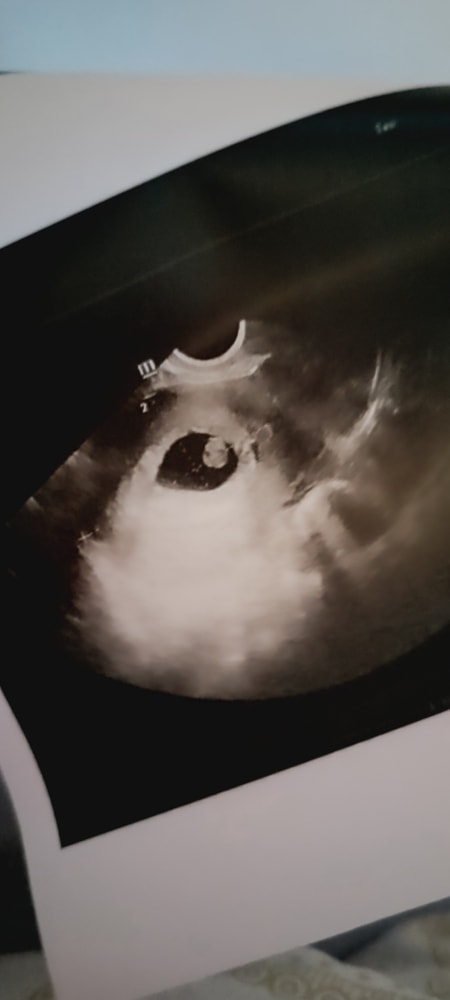

УЗИ в 7 недель и 5 дней

В смысле какова вероятность? 2 сердца же,вероятность 100% или я чего не догоняю

У вас практически 100% )))